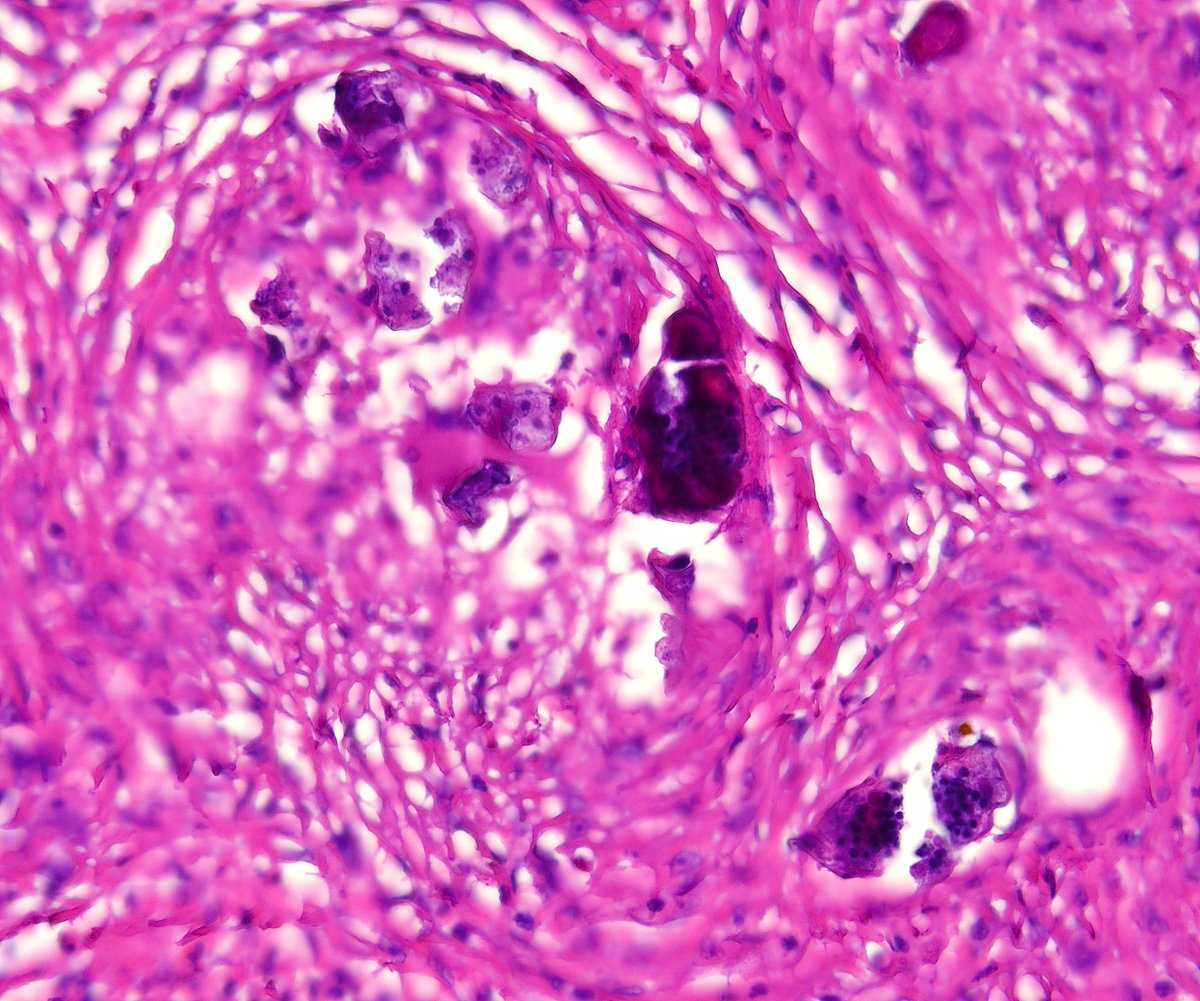

What is this bubbly cell? What are the pink dots in the cytoplasm? Diagnosis? Answers ✅ youtu.be/DqLK6ZvNXTU #pathology #pathologists #pathTwitter #dermpath #dermatology #dermatologia #dermtwitter

What is this bubbly cell? What are the pink dots in the cytoplasm? Diagnosis?

Answers ✅ youtu.be/DqLK6ZvNXTU

#pathology #pathologists #pathTwitter #dermpath #dermatology #dermatologia #dermtwitter